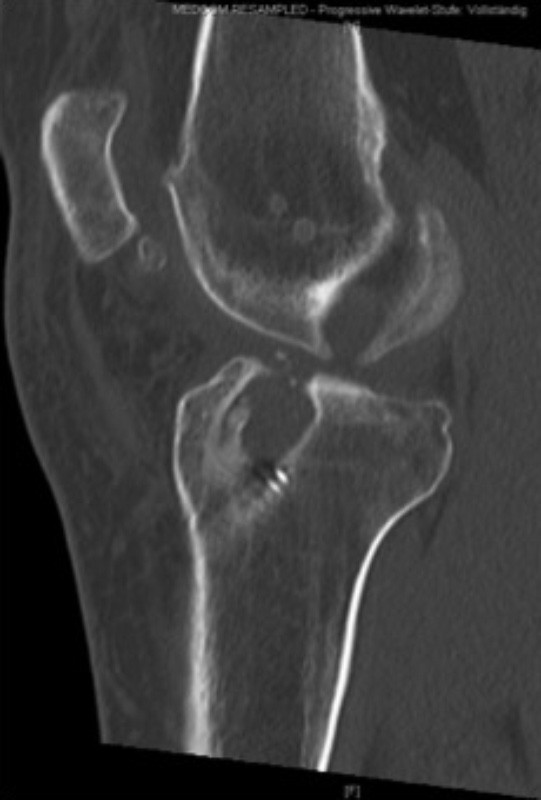

Auffüllung geweiteter Bohrkanäle mittels Spender- oder Eigenknochen

Kommt es nach einer Kreuzbandplastik zu einer erneuten Instabilität des Kniegelenkes ist häufig eine nicht ganz optimale Position der ursprünglichen Bohrkanäle oder eine Weitung der Kanäle im Laufe der Zeit die Ursache. In diesen Fällen müssen die Bohrkanäle zunächst aufgefüllt werden um die sichere Anlage, neuer Bohrkanäle zu ermöglichen. Hierfür wird zunächst das alte Transplantat im Rahmen einer Kniegelenksspiegelung aus den Bohrkanälen entfernt und die Kanäle ausgebohrt. Zur Auffüllung der Kanäle wird in der Regel Spenderknochen verwendet. Im Gegensatz zu künstlichem Material führt dieser innerhalb von 3 Monaten zu einer optimalen Durchbauung. Die Gefahr einer Abstoßung oder einer Infektion kann durch die Behandlung des Knochens vor der Implantation annähernd ausgeschlossen werden.

Die Einheilung des Knochens wird 3 Monate nach der Implantation mittels eines CTs überprüft. Anschließend kann in einem zweiten Eingriff eine erneute Kreuzbandrekonstruktion durchgeführt werden.